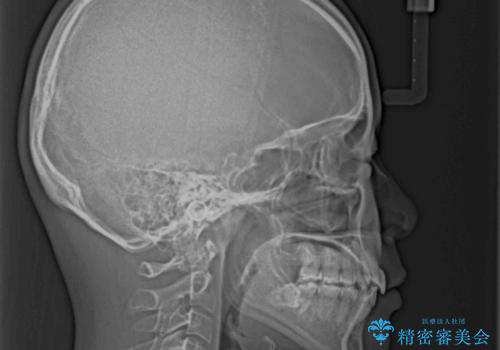

短期間で口元の突出感を改善 ワイヤー装置での抜歯矯正

上下左右4本抜歯する場合には、通常2年から2年半ほどの期間を要しますが、僅か1年半で終了することができました。